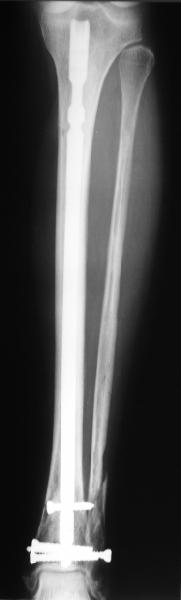

A typical case is attached, also an image with intra-op reduction obtained by a small wire distractor, in the moment of insertion a Poller wire in AP direction. Fixation by a SIGN nail. Despite the fibula was not fixed healing was obtained with the unchanged alignment.

At least both the ankle mortise and tibial alignment look acceptable, don't they?

TDVC> Would that have been eliminated by fibula plating?

I am just trying to illustrate that prevention of 1)tibial valgus and 2)loss of reduction can be provided without fibular plating. Small changes of conventional nailing techniques allow to maintain reduction of the tibia reliably without adjunctive fibular stabilization.

In delayed cases acute length restoration performed only in the tibia may leave the fibula shortened thus change the mortise. So it is reasonable to restore length of both bones simultaneously by distractor and fix the fibula not with open reduction and plating but just by a single perQ screw. Example attached.